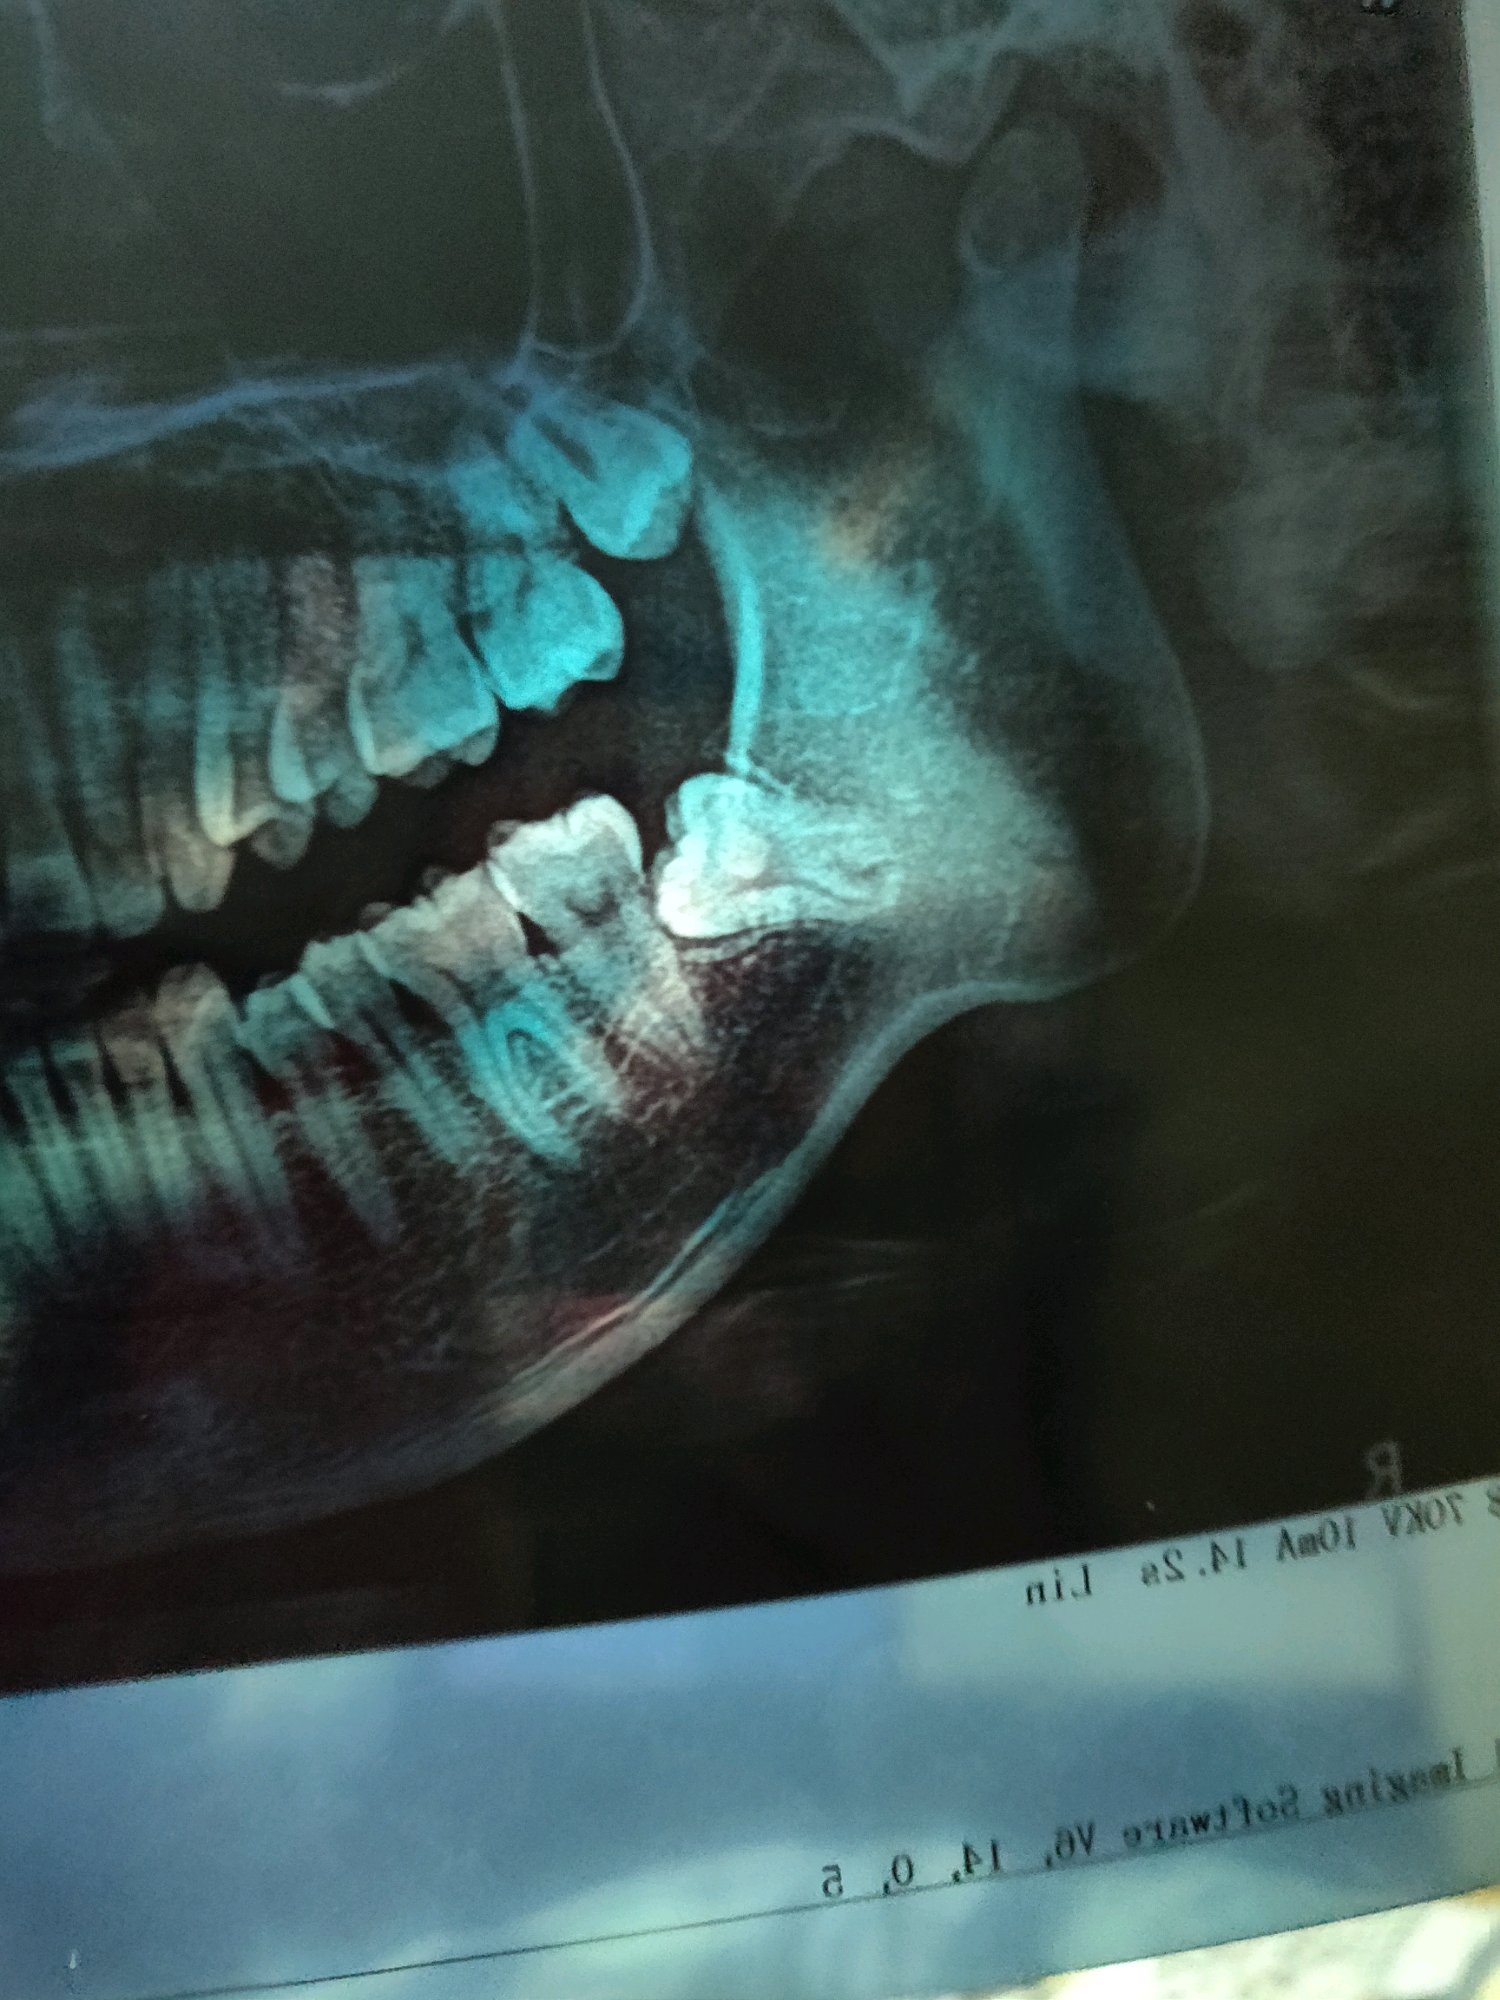

两颗横向阻生智齿,完全埋肉里没露头的骨埋伏

3月28号# 红色圈起来这颗今天下午拔了,削了点骨,缝了几针,十分钟左右。医生技术五星好评,如果不是他非要我留一侧吃饭,我估计两边一起拔了。

4月4号拔另一侧,另一颗有三个牙根,神经从三个牙根正中间穿过。危险系数相当高,祝我好运了。

神经的具体位置是别的扫描图放大看的,这个图看不出

4月4号拔了左侧智齿(ct上是反过来显示的钱、所以在右边)

这颗智齿危险系数非常大,有三个牙根,神经管从中间几乎是贴着三个牙根穿过(如图二所示),如果伤到神经面部会失去知觉。

图3-5: 是3月28号拔的右侧智齿(从去骨到缝合仅用了几分钟)

图6-7是4月4号的智齿,这个因为危险程度大,时间略长用了十多分种,李明院长医术十分精湛,完全没有伤到神经(忍不住称赞一下)